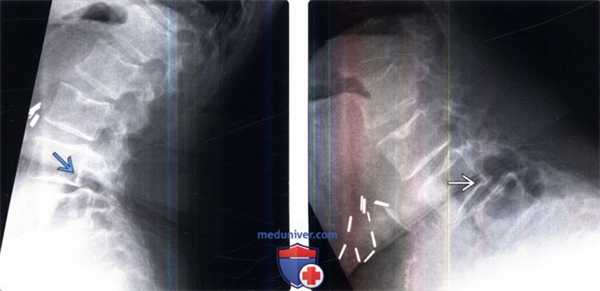

На рентгенограммах и снимках мультиспиральной компьютерной томографии (МСКТ) шейного отдела позвоночника выявлены кифотическая деформация, нестабильность позвоночника, при проведении МРТ отмечены признаки передней компрессии, деформации спинного мозга (рис. 2). Рис. 2. Рентгенограмма и снимок МСКТ позвоночника (сагиттальная проекция), МРТ позвоночника (сагиттальная и аксиальная проекции) — тип В деформации позвоночника.

Больной Х., 62 года, поступил в клинику с жалобами на слабость и боли в руках, слабость и неловкость в ногах, преимущественно в левой, нарушение функции тазовых органов по типу задержки, боли в надплечьях, шее, затылке. Из анамнеза известно, что онемение в пальцах беспокоит около 10 лет. Ухудшение состояния наблюдается в течение нескольких лет, в ближайшие 2 мес перед госпитализацией усилилась неврологическая симптоматика без видимых причин. При осмотре: практически не ходит из-за слабости в ногах, действия, связанные с мелкой моторикой рук, невозможны. Пальпация остистых отростков болезненна. Отмечается ограничение объема движений в шейном отделе. Поднятие и заведение левой руки за голову и спину резко болезненно, с появлением судорог, усилением пареза и онемением руки. Чувствительные расстройства в виде гипестезии в руках до анестезии в дистальных отделах. Смешанный тетрапарез до 3 баллов в руках и 4 баллов в ногах. Сухожильные рефлексы на руках снижены. На нижних конечностях рефлексы резко повышены до клонуса стоп. Патологические рефлексы на нижних конечностях. Брюшные рефлексы симметрично повышены. Нарушение функции тазовых органов по центральному типу. Данные интроскопии (МРТ, МСКТ) представлены на рис. 4. Рис. 4. Рентгенограмма, МСКТ позвоночника (сагиттальная проекция), МРТ позвоночника (сагиттальная и аксиальная проекции) — тип В деформации позвоночника.